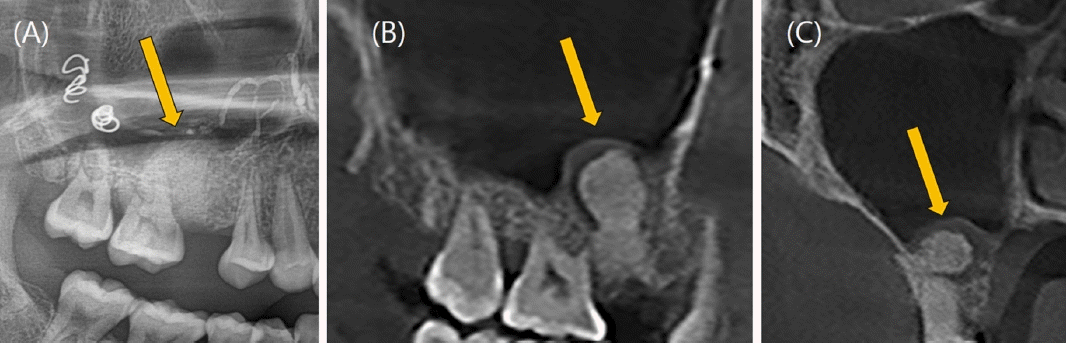

26세 여성이 수개월 전부터 발생한 원인미상의 지속적인 우측 상악 후방부의 잇몸 출혈을 주소로 의뢰되어 구강악안면외과 외래에 내원하였다. 빈혈 이외의 특이 병력은 없었으며, 콘빔 전산화단층촬영(Cone-beam Computed tomography, CBCT)과 파노라마영상을 포함한 단순 진단 영상에서 우측 상악 제2소구치와 제1대구치의 치근단 부위에 직경 12mm의 원형 낭종(Cystic lesion)으로 보이는 병소와 이에 동반된 협측 치조골의 골 침식(Bone erosion)이 관찰되었다(Fig. 1). 병소와 연관되어 있는 치아인 우측 상악 제2소구치와 제1대구치는 전기 치수검사(Electric pulp test)상 생활력이 있었으며, 필요시 술 후에 증상관찰 후 근관 치료를 시행하기로 계획하였다. 방사선 소견 상 반구형의 낭성 종괴, 부드럽고 매끈한 외부경계로 인해 상악동의 점액성 저류낭종(Maxillary mucous retention cyst)일 가능성도 존재했으나 콘빔 전산화단층촬영(CBCT) 상에서 치근부와 연결점이 보인다는 점에서 확률이 낮다고 판단했다[14]. 결국 치근단낭종으로 임시 진단을 내린 후 일주일 뒤 구강악안면외과 외래에서 낭종 적출술을 계획하였다. 빈혈의 기왕력이 있어 일반혈액검사를 실시한 결과, 헤모글로빈 6.7 g/dL, 혈소판 321,000/uL, 프로트롬빈 시간(Prothrombin Time, PT) 13.2 sec, 82.3%, INR 1.11, activated PTT(Partial Thromboplastin Time) 27.9로 외래 수술 시행 전 낮은 헤모글로빈 수치가 관찰되었지만 어지럼증과 같은 임상적 증상은 없었다.구강악안면외과 외래에서 1:100,000 에피네프린이 함유된 2% 리도카인(Lidocaine) 국소마취 하에 낭종 적출술을 시도했으나 수술 중 기구를 치근단 병소 부위로 접근하자마자 대량 출혈(Massive bleeding)이 발생하였으며, 국소적 지혈을 시도하였으나 전혀 지혈이 되지 않았다. 저혈량성 쇼크(Hypovolemic shock) 위험성이 있어 수술을 중단 후 응급실로 이송하였으며, 즉각적으로 적혈구 수혈 및 체액량 보존을 위해 0.9% 생리식염수로 정맥내 수액 공급을 진행하였다. 이어 구내에 발생한 출혈을 조절하기 위해 이어 영상의학과에 의뢰하여 접형구 개동맥(Sphenopalatine artery)과 상악후상치조동맥(Posterior superior alveolar artery)을 대상으로 색전술(Embolization)이 시행되었다(Fig. 2). 응급색전술은 겔폼(Gelfoam), 33% 아교(Glue), 코일(Coil)을 사용하였으며, 성공적으로 출혈을 조절할 수 있었다. 색전술을 시행한 다음날 적절한 혈관 폐색이 이루어졌는지 확인을 위해 전산화 단층 혈관 조영술(Computed tomographic angiography) 촬영을 진행하였다. 접형구개동맥이 폐색되어 있음을 확인하였고, 공급혈관(Feeding vessel) 내에 코일이 적절히 위치해 있었으며, 후상치조동맥에서 기원한 분지 내에서 병변 주변으로 이루어진 glue casting이 관찰되었다(Fig. 3). 이러한 영상 판독 결과를 통해 병변의 혈관 공급이 성공적으로 차단되었음을 확인하였다. 골내 혈관종의 다양한 방사선소견으로 인해 초기에 치근단낭종으로 오인되었음을 확인하였고, 이에 따라 낭종적출술이 아닌 골내혈관종의 수술적 절제를 계획하였다.색전술을 시행한지 이틀 째에 국소마취 하 혈관종의 절제술이 이루어졌다. 협측으로 접근하여 15번 외과용 칼(No.15 Surgical blade)와 골막기자(Periosteal elevator)로 조심스럽게 골막점막피판을 거상한 후에 종양을 주변 조직으로부터 박리하여 모스키토 지혈겸자(Mosquito forcep)로 종양을 제거하였다. 이 과정에서 치근단이 병변과 긴밀하게 연접하고 있는 상악 우측 제2소구치의 경우, 협측 골이 상당히 소실되어 있는 상태로 3도의 동요도를 보여 결국 발치를 하기로 결정하였다. 골 결손 부위와 발치와는 추후 임플란트 식립을 고려해 이종골 이식재와 흡수성 차폐막을 적용해 골이식을 시행하였다.수술적 제거 이후 2개월 추적관찰에서 재발 또는 잔여 증상은 관찰되지 않았다. 임상검사 및 방사선 영상검사에서 골 치유가 만족스럽게 이루어졌으며, 우측 상악 제1대구치에서 동요 또는 타진 통증 없이 환자는 무증상 상태를 유지하였다(Fig. 4). 수술 3개월 후 환자는 안정적인 골 치유와 충분한 각화 치은이 생성된 것을 확인되어 우측 상악 제2소구치부위의 고정체 식립을 위한 임플란트 1차 수술을 시행하였다. 이어 3개월 뒤 임플란트 치유지대주를 연결하는 임플란트 2차 수술 및 상부 보철물 수복을 완료하였으며, 경과 관찰 시 수술부위의 별다른 증상이나 재발의 증거는 없었고, 합병증은 발생하지 않았다.

Figure 2.

(A) External carotid angiography before embolization shows the sphenopalatine and posterior superior alveolar arteries. (B) Post-embolization angiography reveals a reduction in mass size.